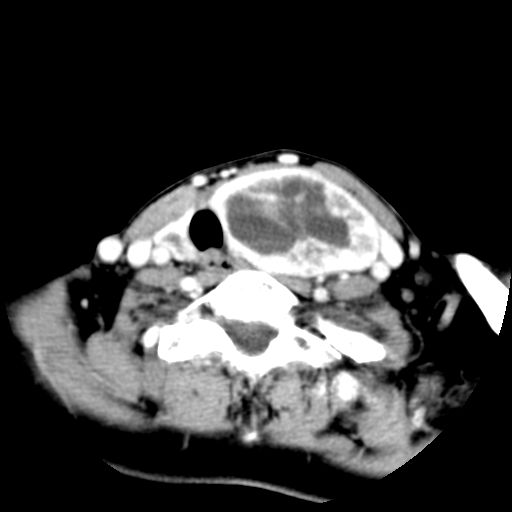

女  53岁  左侧甲状腺肿物3年,近2月明显增大。病理稍后发。

左侧甲状腺内见有一较大类圆形低密度区,边缘清楚光整,增强有一定强化,但仍较正常甲状腺组织强化弱,左侧甲状腺周围组织明显受压移位,且周围组织界限存在,周围组织间隙内未见肿大淋巴结,结合病史考虑为良性病变,左侧甲状腺腺瘤可能大。

左侧甲状腺内见有一较大类圆形低密度区,边缘清楚光整,增强有一定强化,但仍较正常甲状腺组织强化弱,左侧甲状腺周围组织明显受压移位,且周围组织界限存在,周围组织间隙内未见肿大淋巴结。

考虑:甲状腺囊腺瘤

双侧都有,最大病灶在左侧,其包膜和灶内部都有明显的强化,提示其血供丰富。我首先考虑是良性占位,以腺瘤可能性大。

左侧甲状腺内见有一类圆形低密度区,边缘清楚光整,可见明显增强,间隔亦可见增强,且与周围组织分解清晰,周围组织间隙内未见肿大淋巴结。右侧亦可见类似表现。考虑甲状腺腺瘤。

手术病理证实:双侧腺瘤样甲状腺肿。